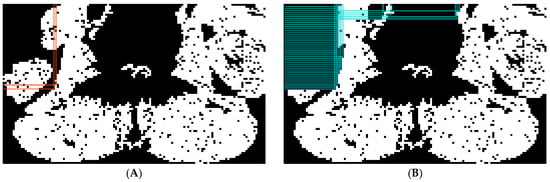

2.5.1. Preprocessing

2.5.2. Abdominal Muscle Segmentation